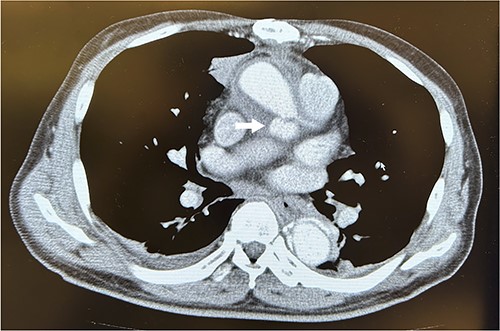

A 67-year-old male patient underwent emergency total arch replacement 11 years prior to acute aortic dissection. Nine years later, the patient underwent descending aortic replacement surgery because of enlargement of the descending aorta. Two years later, the Bentall procedure was performed for chronic dissection of the aortic root and subsequent enlargement. We identified the dissected aortic wall of the coronary ostium, which was thickened (Fig. 1) and created a coronary button for anastomosis. The patient presented with haemoptysis was diagnosed with a pseudoaneurysm in the left coronary artery using computed tomographic angiography (Fig. 2), and was referred to our hospital for surgery.

Computed tomography scans revealed a pseudoaneurysm from the left coronary artery. The arrow indicates the pseudoaneurysm.